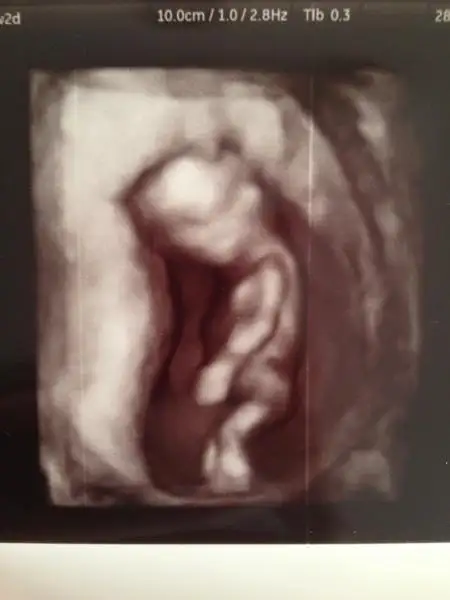

Bugün harika birgün 2 bebişimizinde cinsiyetini öğrenebilirizTabii sağlıklı haberlerinidee

deragün niye korkuyosun ki canım. kocaman oldu bebişin. iyidir inşallah. strese girme öyle![]()